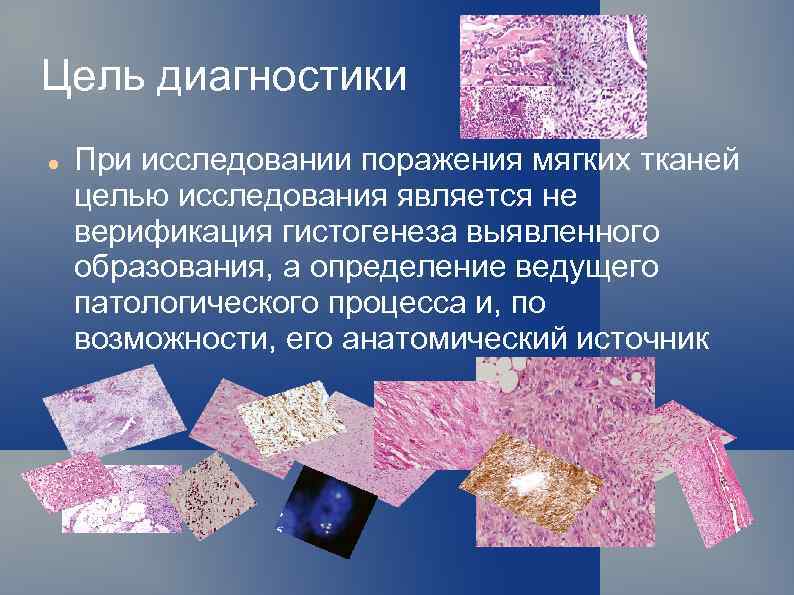

Цель диагностики При исследовании поражения мягких тканей целью исследования является не верификация гистогенеза выявленного образования, а определение ведущего патологического процесса и, по возможности, его анатомический источник